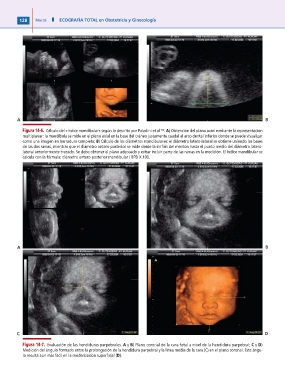

Figura 14-6. Cálculo del «índice mandibular» según lo descrito por Paladini et al .(74) A) Obtención del plano axial mediante la representación

multiplanar: la mandíbula se mide en el plano axial en la base del cráneo justamente caudal al arco dental inferior donde se puede visualizar

como una imagen en herradura completa; B) Cálculo de los diámetros mandibulares: el diámetro latero-lateral se obtiene uniendo las bases

de las dos ramas, mientras que el diámetro antero-posterior se mide desde la sínfisis del mentón hasta el punto medio del diámetro latero-

lateral anteriormente trazado. Se debe obtener el plano adecuado y evitar incluir parte de las ramas en la medición. El indice mandibular se

calcula con la fórmula: diámetro antero-posterior mandibular / BPD X 100.

Figura 14-7. Evaluación de las hendiduras parpebrales. A y B) Plano coronal de la cara fetal a nivel de la hendidura parpebral; C y D)

Medición del ángulo formado entre la prolongación de la hendidura parpebral y la linea media de la cara (C) en el plano coronal. Este ángu-

lo resulta aún más fácil en la renderización superficial (D).